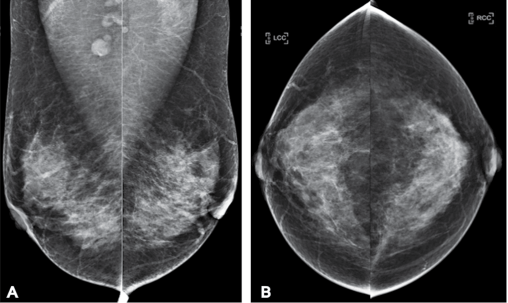

Examples of a screening mammography study. One patient, four pictures. One cancer, believe it or not. It isn’t the round bits at the top of A. It is the grey bit in the left breast that looks just like the rest of the grey bits. Mammography is hard and subtle.

This paper is interesting. The title kind of says everything we want to know – they are applying deep learning to look at mammograms with multiple different images per case, at high resolution, applied to a screening population.